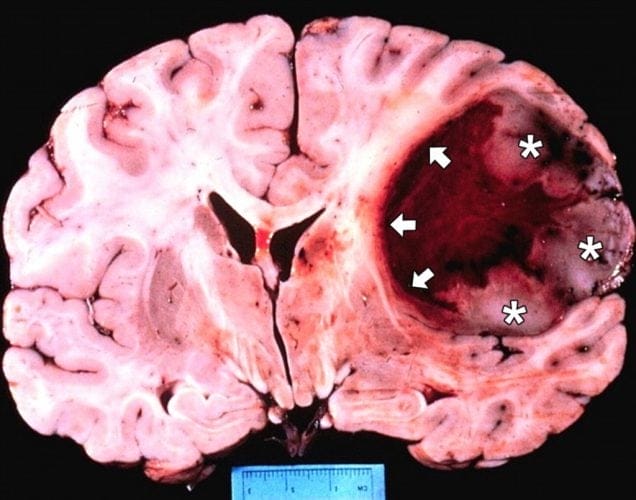

Гліобластома — це одна з найнебезпечніших форм пухлин головного мозку, яка вражає гліальні клітини. Вона характеризується стрімким ростом, високою здатністю до інфільтрації тканин і стійкістю до терапії. Навіть після хірургічного втручання, променевої або хіміотерапії пухлина часто повертається. Середній термін виживаності після встановлення діагнозу становить приблизно 12–15 місяців, попри інтенсивне лікування.

Один із механізмів, який допомагає гліобластомі виживати й поширюватися, — це активація певного метаболічного шляху, пов’язаного з ферментом 2-аміноетантіолдіоксигеназа (ADO). Цей фермент сприяє утворенню гіпотаурину — сполуки, що підтримує життєздатність пухлинних клітин та їхню стійкість до кисневого голодування й стресу. Раніше не існувало затверджених ліків, здатних пригнічувати дію ADO.